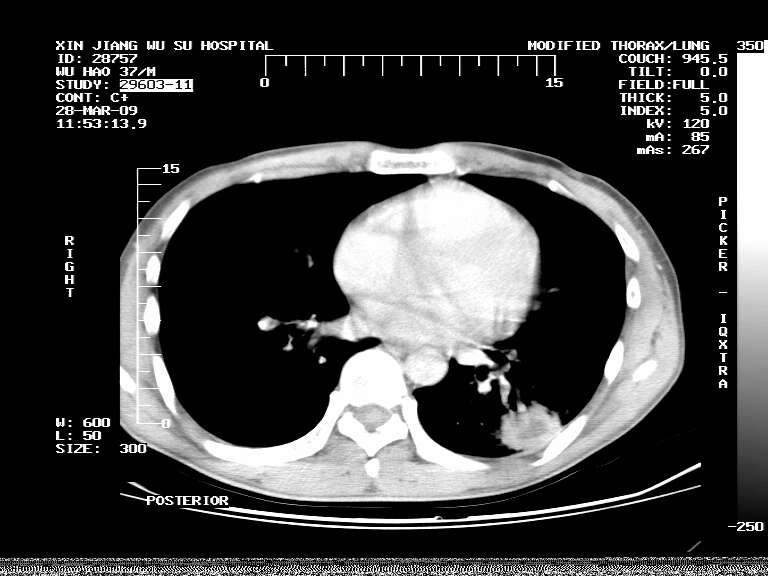

男,37岁,体检胸透发现阴影。

患者体检发现 无症状 左肺下叶占位,边缘模糊,可见血管聚束、分叶、胸膜牵拉,增强呈不均匀性强化。 首先考虑左肺下叶周围型肺癌,建议穿刺活检。

患者体检发现 无症状 左肺下叶占位,边缘模糊,可见血管聚束、分叶、胸膜牵拉,增强呈不均匀性强化。 首先考虑左肺下叶周围型肺癌,建议穿刺活检。支持!

左肺下叶见一结节病变,边缘欠清不光滑,与胸膜粘连且胸膜局限性增厚,注药后呈环形强化,动脉期壁呈明显点环状强化,静脉期壁强化减低,中心密度低无强化,灶周无明显的卫星灶和水肿区(晕征)---考虑周围性肺癌,不除外感染性病变,建议穿刺活检。

左肺下叶软组织病灶,密度较高,内见点状钙化,其周围见子灶,邻近胸膜扁平样增厚.c+病灶强化明显,中心强化弱.诊断:左肺下叶结核瘤.

左肺下叶大片实变影,内靠胸膜见不规则更高密度结节灶,边缘强化,相邻胸膜增厚,胸膜下脂肪线存在。考虑炎症,结核可能。